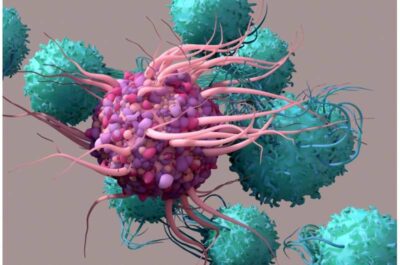

Tumori freddi-Immagine: le cellule dendritiche (viola) fanno parte della prima linea di difesa del sistema immunitario contro il cancro e le infezioni. Possono fagocitare e digerire le cellule tumorali e quindi presentare i pezzi (antigeni) per attivare un esercito di cellule T (verde acqua). Credito: Shutterstock-

I ricercatori hanno poi esplorato i modi per potenziare le cellule dendritiche, parte della prima linea di difesa del sistema immunitario contro il cancro e le infezioni. Le cellule dendritiche possono fagocitare e digerire le cellule tumorali e quindi presentare i pezzi (antigeni) a un esercito di cellule T. Ciò attiva le cellule T per colpire specificamente il tumore.